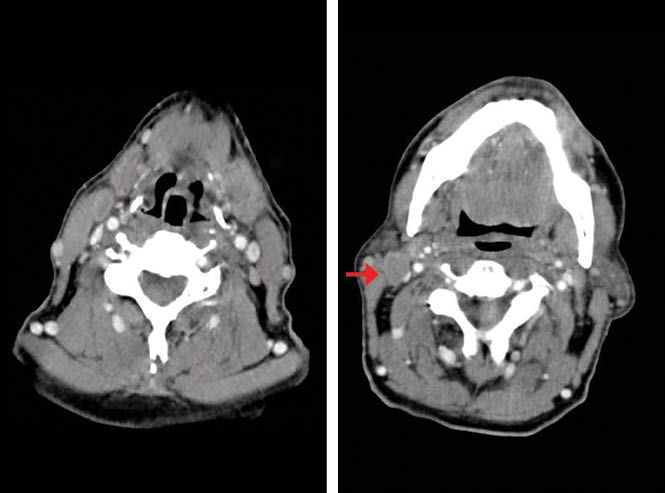

Ten weeks after the patient finished CRT, a CT scan reported persistence of cervical adenopathies and CR of the primary tumor (Figure 1c). A laryngoscopy described edema of the lateral walls of the hypopharynx, base of the tongue, and uvula, without evidence of tumor. The pathological findings revealed unspecific chronic inflammatory changes.

Figure 1C. Post chemoradiotherapy (CRT) contrast enhanced CT scan shows postradiotherapy changes in the hypopharynx, no evidence of the primary tumor (left). Right cervical matted nodes (right).